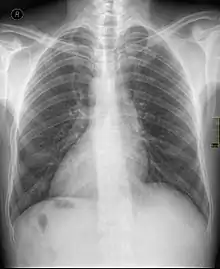

Dextrocardie

La dextrocardie est une malformation de naissance dans laquelle le cœur se trouve dans la moitié droite du thorax. La pointe du cœur est aussi orientée à droite.

Cœur normal